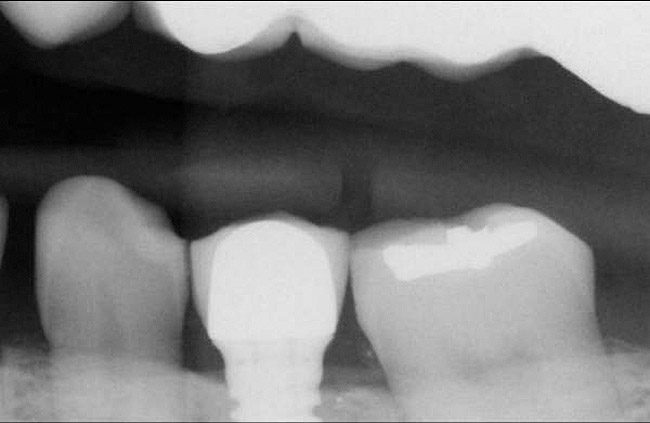

Figure 12  Horizontal spacing needed between the natural tooth and the implants and between the adjacent implants.

Figure 12

Horzontal Components of Implant Placement

The horizontal aspect of implant spacing is critical to avoid bone loss on adjacent teeth or implants. Single-tooth implants should be placed 1.5 mm to 2 mm from the adjacent teeth,19,20 and implants should have at least 3 mm of space between them21 (Figure 12). By keeping a minimum 1.5-mm distance from the adjacent tooth and a minimum distance of 3 mm between adjacent implants, angular defects resulting from crestal bone remodeling can be kept from becoming horizontal defects19-22 (Figure 13). This distance allows the bone on the adjacent tooth to stay at its current level. Conversely, if bone loss on the adjacent tooth or implant occurs, the bone loss will not affect the adjacent tooth or implant. This is especially critical in the anterior regions of the mouth where papilla height is more important for an esthetic result.23-27